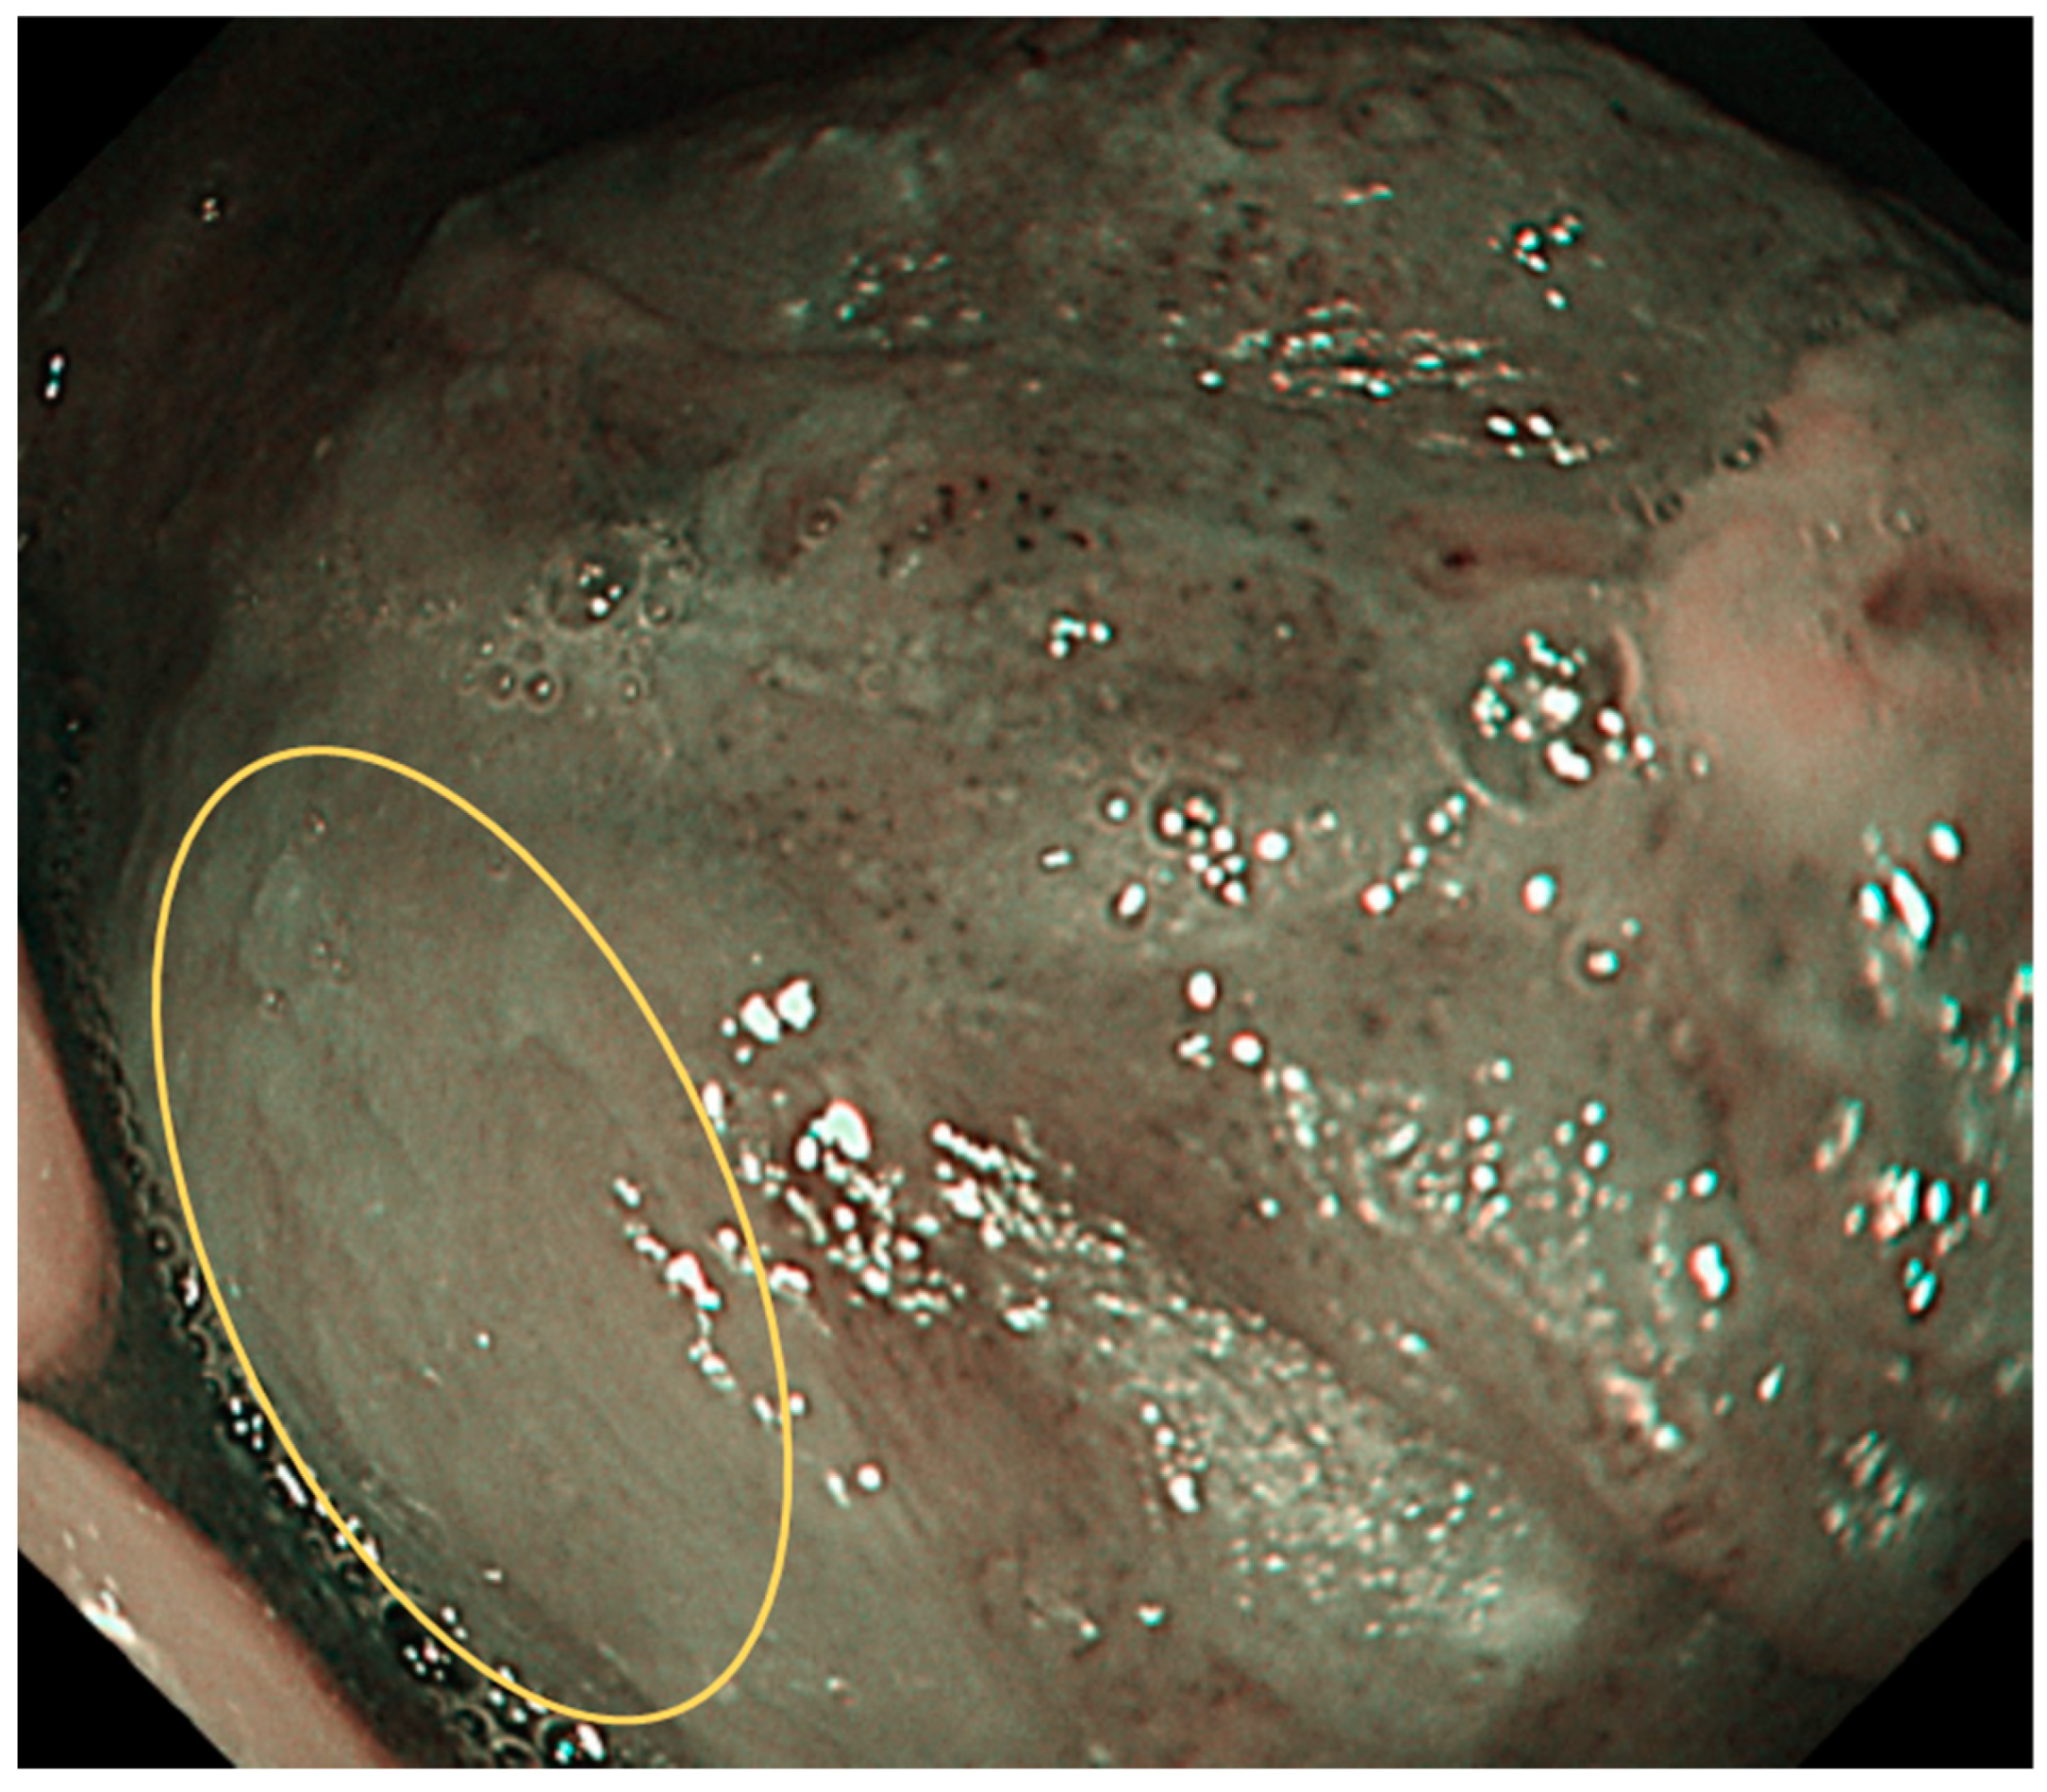

7. Interpretation of IPCLs

8. Limitations of NBI Magnification Endoscopy